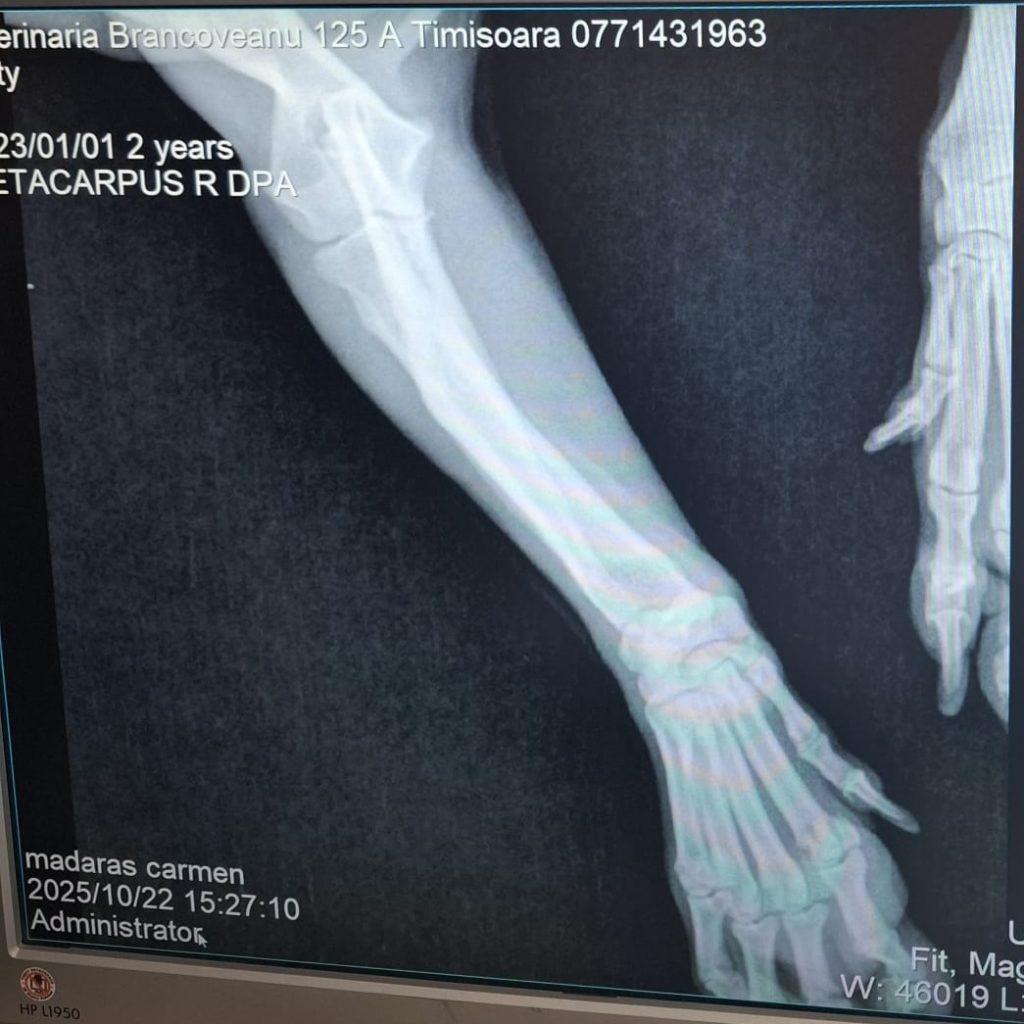

Licas ist ca. 11/24 geboren, etwa 30 cm groß und wiegt ungefähr 7 kg. Er wurde gemeinsam mit seiner Mama verlassen auf einem Feld in Rumänien gefunden. Eine Tierschützerin hat die zwei aufgenommen – das war bereits im Oktober letzten Jahres. Doch Licas brachte ein schweres Schicksal mit: Sein Vorderbein ist gelähmt. Nach dem Röntgen stand fest – eine Amputation oder eine Prothese könnten ihm helfen, schmerzfrei und unbeschwert durchs Leben zu gehen.